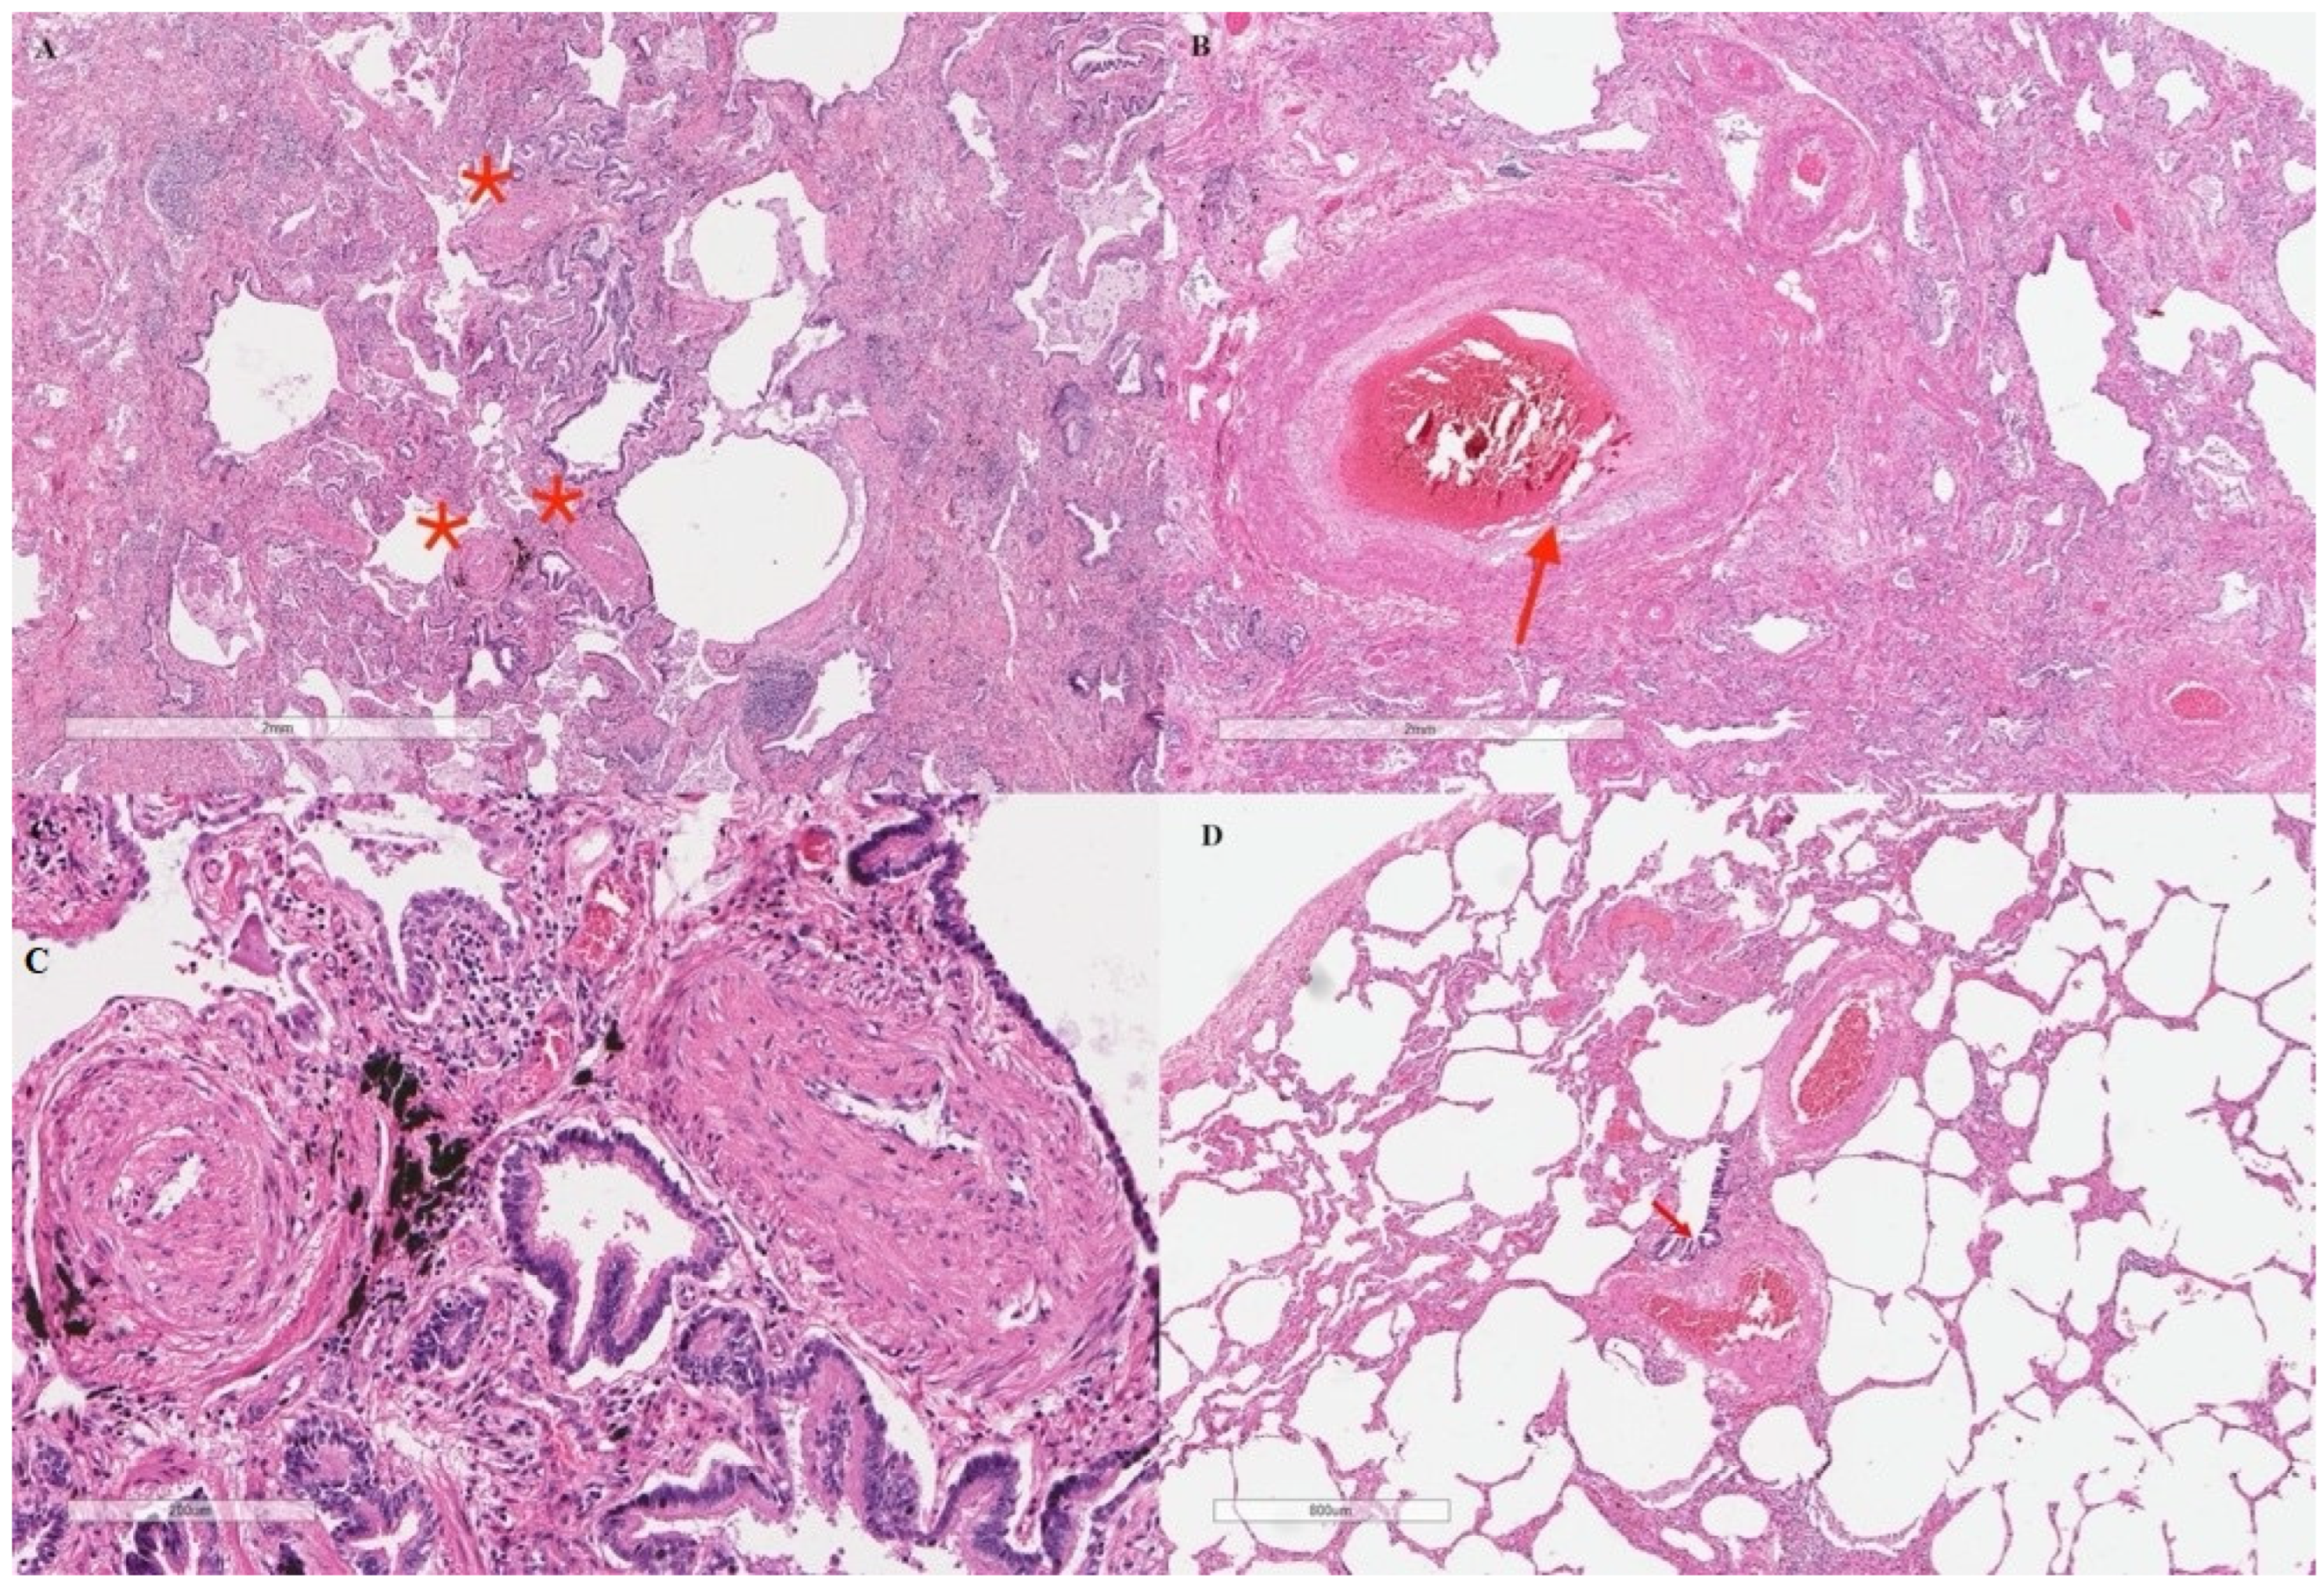

2. Case Presentation

3. Discussion and Conclusions